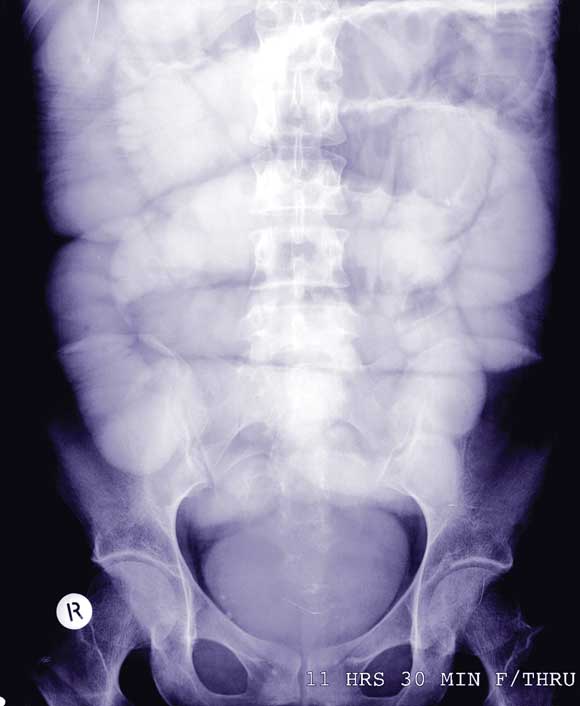

A Gastrografin meal (Schering Pty Ltd, Sydney) and follow-through showed complete small bowel obstruction (Box 1). Subsequent laparotomy revealed a 2.5 × 5 cm bezoar in the distal small bowel, about 60 cm from the ileocaecal valve (Box 2). The bezoar was manually fragmented and passed through the ileocaecal valve into the caecum. The patient recovered well after the operation, and was discharged with psychiatric follow-up.